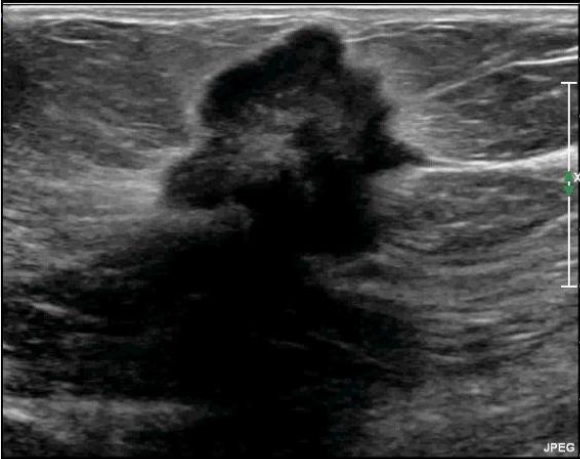

Q

Sugestivo de… ?

A

Maligno